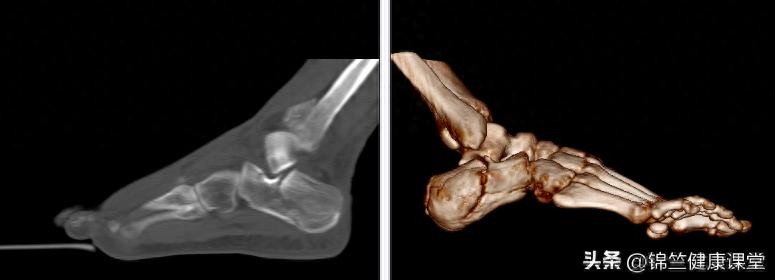

华山骨科现分为脊柱外科、关节外科、足踝外科和创伤骨科四个亚专业组,医疗服务范围既包括骨科各类疾病的常规诊治,又涵盖骨骼运动系统的各类严重畸形及肿瘤性疾病的系统治疗。逐渐形成了以脊柱退变性疾病规范化与微创化诊疗、髋膝肩肘关节置换、足踝部严重畸形矫正、四肢复杂骨折处理为代表的临床特色诊疗技术。